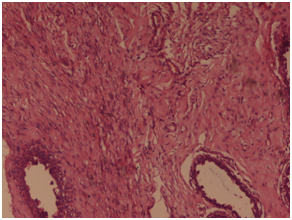

Figure 2 On microscopy, sheets or whorls of tumor cells was seen with cellular and nuclear pleomorphism, hyper chromatic nucleus and high N/C ratio with prominent nucleoli and moderate amount of eosinophilic cytoplasm. Haematoxylin and Eosin x 40X.